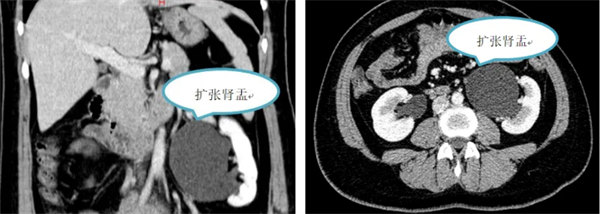

30歲的靳女士來自甘肅,2月前體檢時發現左腎盂重度積水,曾輾轉多家醫院就診,但診斷結果都為選擇手術治療難度大且效果差。若不手術,長期梗阻積水將導致腎臟萎縮失去功能,初為人母的靳女士難以接受,不甘命運的不公,從甘肅不遠千里慕名來到陜西省寶雞市人民醫院,泌尿外四科副主任康啟源接診并收住院。

康啟源積極完善相關檢查,匯報泌尿病院院長李穎毅,考慮到患者只有30歲,初為人母,李穎毅組織全科討論,決定發揮機器人微創和操作精準等優勢,為患者實施創傷小、出血少、恢復快的機器人手術。最終,制定機器人輔助腹腔鏡下實施左腎盂成形術手術方案。

恰逢五一假期,泌尿外科團隊不容猶豫,勞動節當日,泌尿手術團隊為患者成功實施了腎盂成形術,患者取右側斜仰位,于臍左側緣做弧形切口約2.5cm,對接機器人手術系統,手術入路采用經腸系膜入路,直達病灶,精準的定位輸尿管狹窄部位,先“S”形對腎盂及輸尿管進行精細的游離,可見左側腎盂輸尿管連接處明顯迂曲、狹窄,顯露輸尿管狹窄段,長度約1cm,同時裁剪擴大的腎盂,采用可吸收縫線將腎盂最低點與輸尿管最低點進行對接縫合,后置入F5導管可見輸尿管下段通暢,繼續沿輸尿管切緣向腎盂端進行腎盂-輸尿管吻合,經過精準的操作和密切的團隊配合,手術取得了圓滿成功,且未使用輔助孔,手術時間約4小時,術中出血僅約10ml,未留置引流管,患者第二天就下床活動,恢復良好,手術瘢痕幾乎不顯現。